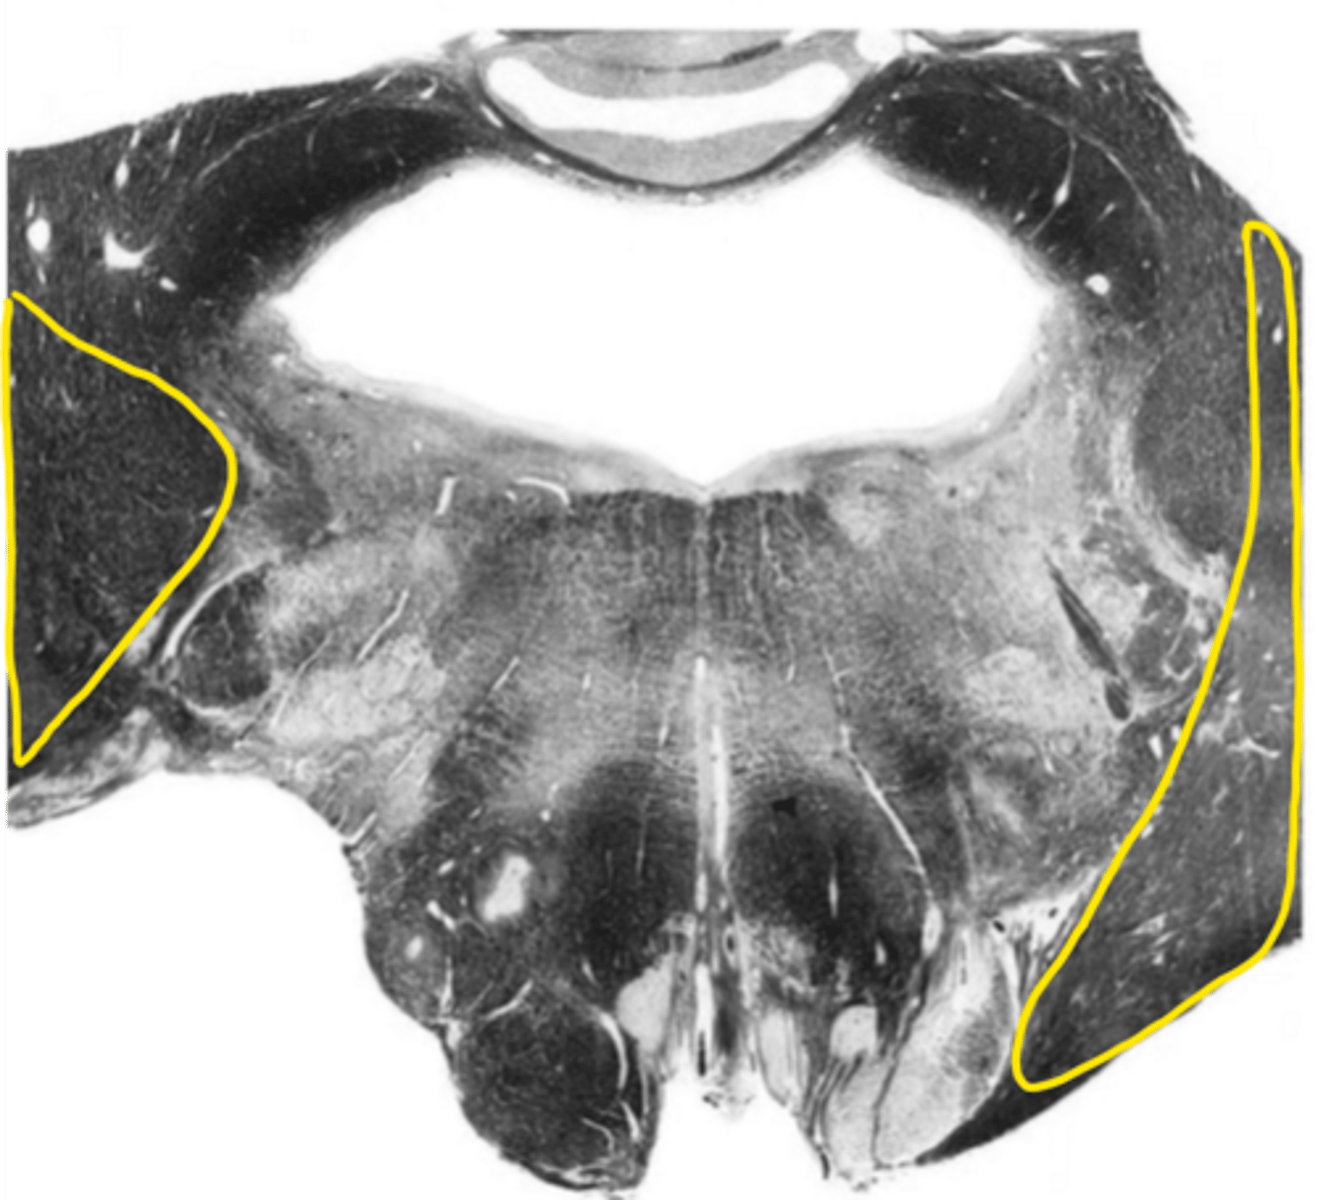

middle cerebellar peduncles

ID the structure

inferior cerebellar peduncles